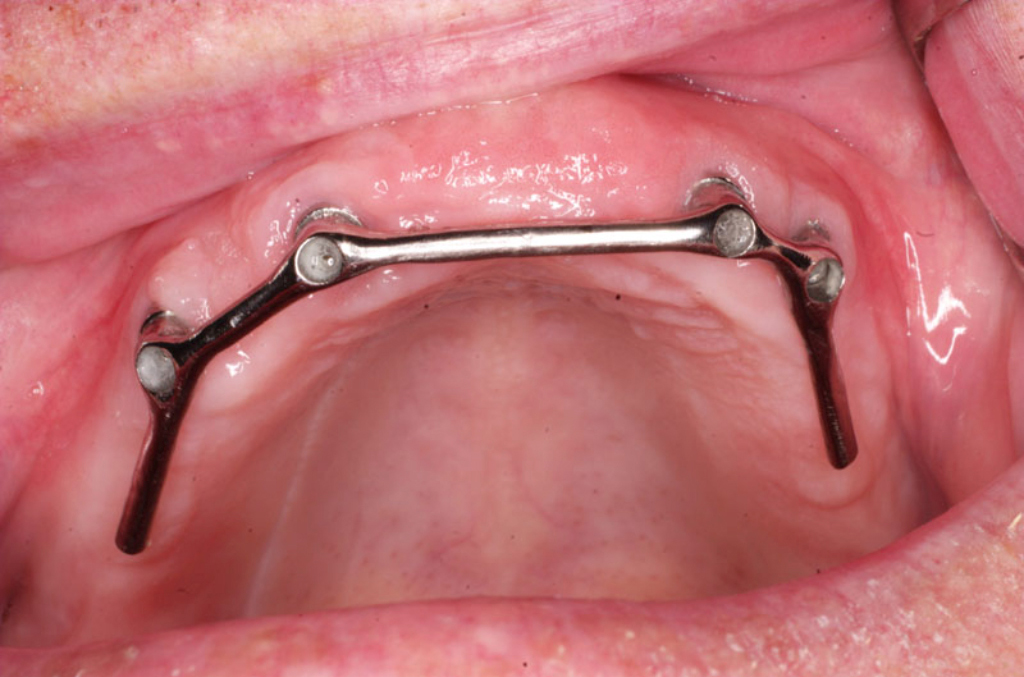

Bezzubá čelist

Třmeny

Bezzubá čelist je hlavní indikací pro ošetření pomocí implantátů. Zejména celkové zubní náhrady v dolní čelisti mají velice nízkou stabilitu a držení díky velkému úbytku kosti.

S pomocí zubních implantátů můžeme díky různým kotevním systémům (třmeny, kulové hlavy, Locatory) zajistit stabilitu a držení protézy nebo při použití většího počtu implantátů zhotovit pevné náhrady – můstky nalepené nebo našroubované na pevno na implantáty.

S těmito typy náhrad můžeme dosáhnout perfektní funkci, výbornou estetiku, fonetiku a současně zajistit u pacienta možnost dobré hygienickou péče a čištění, která je pro životnost implantátů velice důležitá.